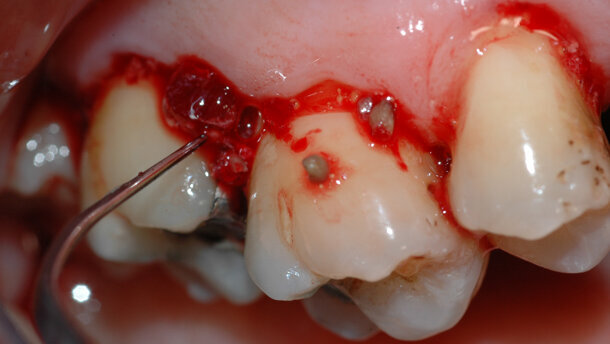

In altre parole, l’obiettivo principale è rimuovere il fattore eziologico, che provoca l’infiammazione, nel modo più efficace e consono alla manualità e alle conoscenze tecniche dell’operatore, pur rispettando esigenze, anche di logica organizzativa, espresse dal paziente. Non si tratta cioè di uno schema rigido cui attenersi, i protocolli possono e devono essere personalizzati e conseguentemente modificati. Se possibile si consiglia di cominciare e completare la fase non chirurgica iniziale (i tre appuntamenti di un’ora ciascuno) entro la prima settimana1, proprio perché una volta individuata la patologia e la sua causa eziologica, rimuovere efficacemente quest’ultima consente di accelerare i processi di guarigione, migliorando probabilmente l’esito del trattamento. I progressi nel campo delle conoscenze di microbiologia parodontale, associati alle migliorie tecnologiche, possono aiutarci sia a capire l’esatta natura delle infezioni parodontali, sia a eseguire un trattamento nel modo più efficace e rapido possibile2. In occasione di ogni appuntamento viene sottoposta a strumentazione parodontale non chirurgica l’intera cavità orale. Ovviamente, la prima seduta sarà dedicata alla strumentazione sopra-gengivale, utilizzando prevalentemente strumenti a ultrasuoni in caso di abbondanti depositi; l’utilizzo del laser deve precedere la strumentazione sotto-gengivale, se si ravvedono indicazioni al suo utilizzo.

È molto importante strumentare ogni volta tutta la cavità orale, al meglio delle nostre possibilità; com’è naturale, non sarà verosimile rimuovere in maniera completa il tartaro sotto-gengivale, soprattutto in occasione del primo appuntamento, viceversa è possibile ridurre i depositi in maniera significativa. È comunque inevitabile lasciare depositi residui, ma questi dovranno essere distribuiti un po’ “a macchia di leopardo”. Importante evitare l’errore di strumentare soltanto i primi millimetri sotto la gengiva, facilmente raggiungibili; ancora peggio, illudersi di strumentare i soli depositi sopra gengivali. Questo provocherebbe il rischio di un episodio acuto, successivo alla seduta di strumentazione parodontale non chirurgica, definito come “effetto polsino”3.